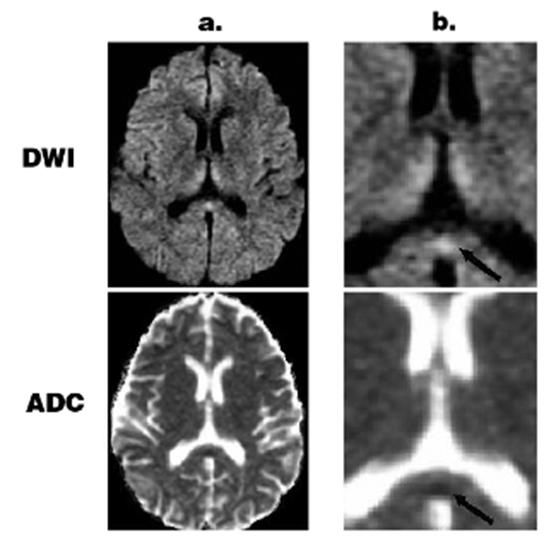

男,26歲,肥胖行減肥手術,術后頑固性嘔吐。臨床表現(xiàn)為淡漠、共濟失調、眼肌麻痹。T2WI示導水管周圍、丘腦背內側高信號。胼胝體壓部彌散受限、ADC減低。